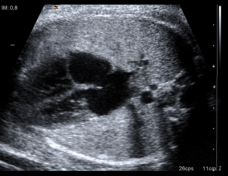

Durante la vida fetal los futuros espacios aéreos del pulmón están llenos de líquido, distinto del líquido amniótico que envuelve al feto. Se trata de un líquido producido en el propio pulmón, y fluye hacia el líquido amniótico o es deglutido.

Durante todo el desarrollo fetal, el pulmón crea líquido constantemente en los alvéolos. Este proceso es crucial para el crecimiento pulmonar fetal. Su presencia en la vía aérea previene el colapso. Hacia el final de la gestación contiene aproximadamente 40-50 ml de líquido.